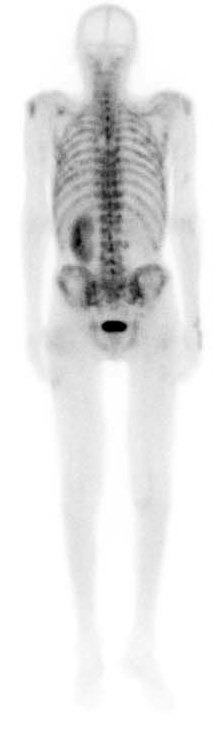

Фото: Остеосцинтиграфия при метастатическом поражение костей скелета

Выполнение лишь одного метода визуализации не позволяет достаточно оценить данную патологию, например, рентгенография и компьютерная томография позволяют детально оценить изменение костной ткани, однако из-за специфики оптических свойств не дают полного представления о мягкотканных структурах и распространении по костномозговому каналу, что требует выполнения магнитно-резонансной томографии. Оценить распространение заболевания в целом позволяет применение различных методов радионуклидной диагностики – остеосцинтиграфии, ОФЭКТ и ПЭТ компьютерной томографии.

Саркомы семейства Юинга – это редкие новообразования, преимущественно молодого возраста. Они имеют повышенную чувствительность к облучению и химиотерапии, требуют комплексного подхода к терапии, которая должна проводиться в специализированных медицинских центрах. В стандартный алгоритм диагностики для первичных новообразований рекомендуется включать сцинтиграфию костей скелета, а также трепан-биопсию костного мозга, потому что наблюдается высокая частота появления метастазов в костях и костном мозге.